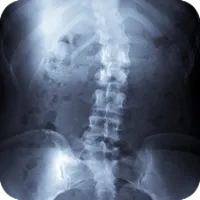

Scoliosis is a condition of the spine that creates lateral curvature, often causing back pain, stiffness and immobility. Scoliosis typically occurs more commonly in females, and begins during growth in childhood. If scoliosis is detected during early childhood, proper treatment can prevent worsening over time. Chiropractic care can help ease the tension of joints and structures of the spine, and alleviate a great deal of the pain associated with scoliosis.

Scoliosis is typically first detected during school screenings, and is generally first visible in the thoracic spine. Vertebrae can rotate, resulting in a hump in the rib cage. Often times this curve makes the hips and shoulders uneven, and can cause low back pain in addition to pain between the shoulder blades.